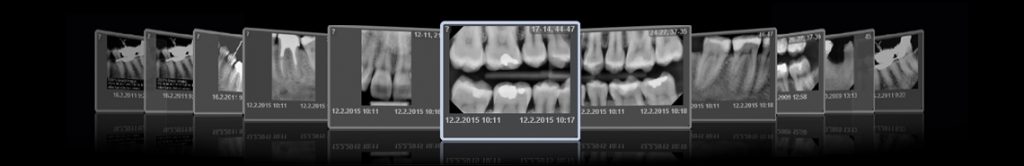

Planmeca ProX intraoral X-ray cihazını Planmeca ProSensor® HD dijital intraoral sensörle birleştirir, kullanıcı dostu özelliğini bir kere daha öne çıkarır. Görüntüler çekimden sadece birkaç saniye sonra ekranda görülür.